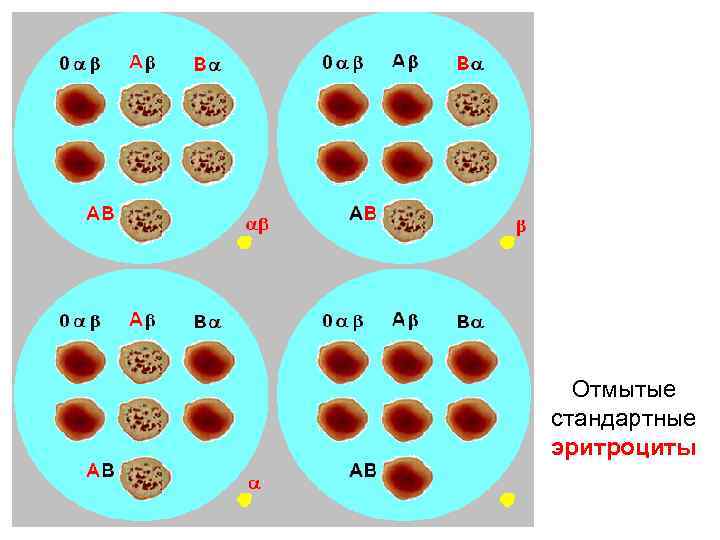

Стандартные сыворотки

Стандартные сыворотки

Отмытые стандартные эритроциты

Отмытые стандартные эритроциты